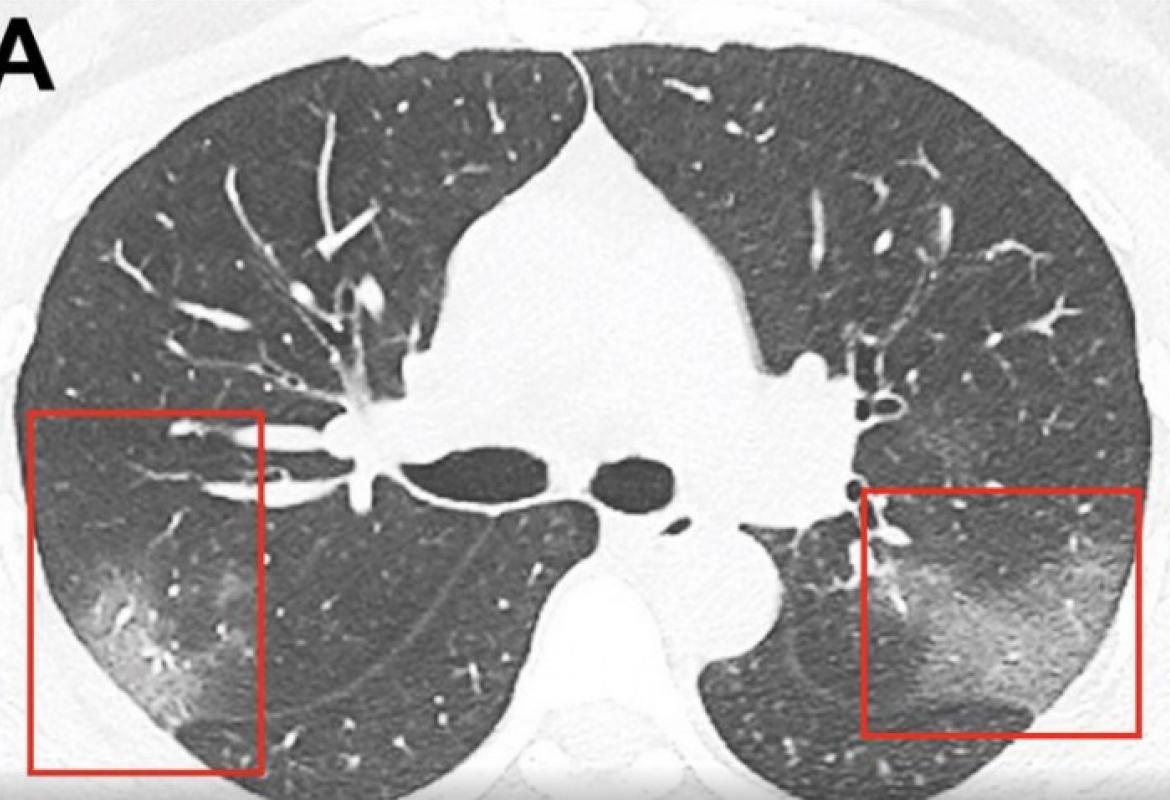

Rendgenski i snimci sa CT skenera, od kojih neki pripadaju 44-godišnjem Kinezu, pokazuju kakve je posledice infekcija imala na pluća.

Virus SARS-CoV- 2 kod ljudi slabijeg imuniteta izaziva bolest pre nego što . Radiografija pluća i srca pokazuje difuzno za- debljanje intersticijuma kod uobičajene intesticijumske pneumonije. Kontrolni CT pregled nakon 6 meseci od završetka zračenja koji pokazuje progresiju parenhimske zamućenosti u . Na radiografiji se uočavaju plućni infiltrati . CT skener direktno ukazuje da su pluća napadnuta od strane SARS- Cov2. A šta ako na skeneru pluća budu Co rads 5 na skali od 6, a taj isti PCR.

CT grudnog koša sa intravenskim ubrizgavanjem kontrasta i softverskom podrškom u vidu "prozora za pluća ", omogućava .